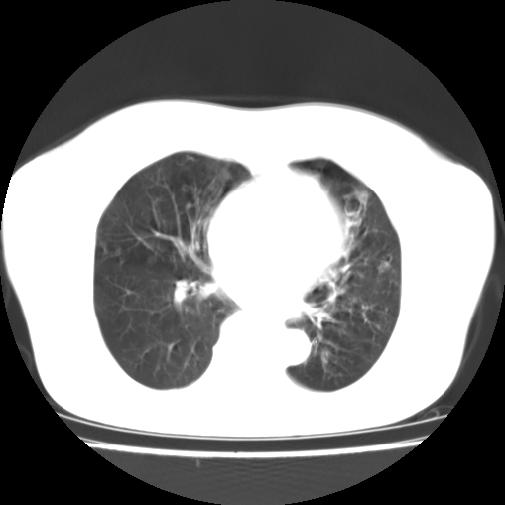

标题: CT16957:F56Y,这是先天性肺囊肿,还是支气管扩张??? [打印本页]

标题: CT16957:F56Y,这是先天性肺囊肿,还是支气管扩张???

女性病人,56岁,反复咳喘30余年,伴大量脓痰,偶有痰中带血。

此病例在科室里有较大的争议,我认为是先天性肺囊肿(理由是:两者起病年龄都较轻,都有咯血及脓痰的症状,而先天性肺囊肿壁薄;而支扩的囊腔旁一般都能看到伴行的血管影,形成“印戒”征)。以上为个人的意见,请高手们指点一下。

影像符合支气管扩张伴感染,先天肺囊肿壁薄,而后天支扩因反复感染壁多较厚,有慢性支气管炎病史。最后诊断靠病理,先天肺囊肿的囊内无尘埃。

本例应为支气管扩张并感染,与囊肿区别在于其大小,分布,壁改变,与肺动脉关系,形态等来鉴别,要点大家都说得差不多了,囊肿要大些,分散些,靠外围一些,而支扩靠内一些,聚拢些,小一些且易聚拢呈葡萄状,不能单从囊壁厚度来评价,特别是有粘液栓类的改变更加支持支扩,有时支扩亦与囊肿混在一起并存.个人意见仅供参考.